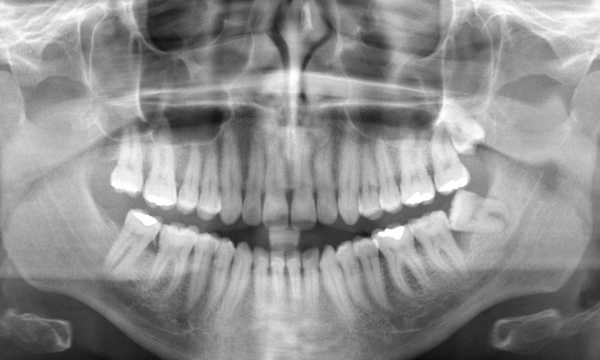

Dotychczas stomatolodzy, przystępując do leczenia endodontycznego czy protetycznego, mieli do dyspozycji głównie badanie rentgenowskie, które pozwala na zobrazowanie struktur zęba i otaczających go tkanek w technologii 2D. To wciąż jedna z najpopularniejszych, bardzo skutecznych metod diagnostycznych, ale ma jedną wadę - zdjęcie w 2D przynosi informację o wysokości i szerokości obiektu, ale nie o jego głębokości, co skutkuje nakładaniem się na siebie struktur.

Uzyskany obraz może być zdeformowany bądź nie do końca czytelny dla dentysty. Pojawiały się problemy z jego interpretacją, co utrudniało postawienie właściwej diagnozy. Szczególnie ważne jest to w planowaniu zabiegów chirurgicznych, leczenia kanałowego, osadzenia implantu w kości czy skomplikowanej ekstrakcji zęba. Z pomocą przyszła nowoczesna technologia.

Tomografia CBCT 3D jest nazywana również tomografią wiązki stożkowej, ponieważ do zobrazowania struktur wykorzystuje promienie rentgenowskie w postaci wiązki stożkowej. Za pomocą tomografii stożkowej można wykonać wirtualną rekonstrukcję 3D uzębienia pacjenta. Pozwala zobrazować wszystkie struktury pod dowolnym kątem: struktury kostne, korzenie zębów, zatoki, naczynia krwionośne czy nerwy.

W przypadkach, gdy CBCT nie jest dostępny lub nie jest zalecany, alternatywne metody diagnostyczne, takie jak zdjęcia panoramiczne, mogą być stosowane, choć oferują one ograniczoną informację w porównaniu do tomografii 3D.